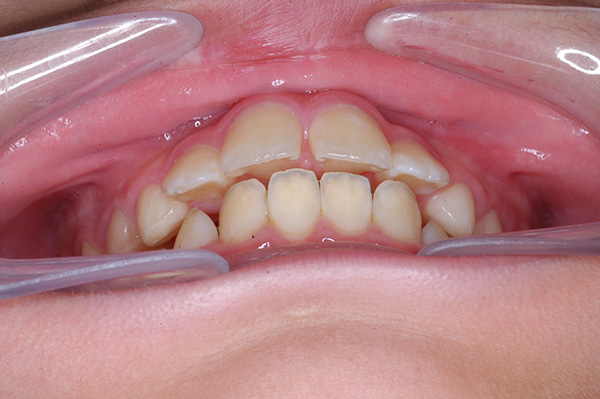

| 口腔内所見 | over jet 5.5mm,over bite 5.0mm,大臼歯関係はⅠ級 、Hellmanのdental ageはⅢBであり上突歯列を呈していた。 |

| セファロ所見 | Sellaに対して下顎頭は後方位だが下顎骨は大きくしっかりとした形態をしており前後的にはⅠ級、垂直的にはロウアングルの骨格形態をしていた。 上顎前歯は唇側傾斜を呈していた。 |

| パノラマ所見 | 上顎左右側犬歯は近心傾斜し側切歯歯根に重なるように認められた。 |

| 批評・予后 | 埋伏歯の牽引を行い位置異常の改善をした結果、適切な犬歯のガイドが得られ、ほぼ緊密な咬合となったように思う。口元の改善を希望された場合は小臼歯抜歯症例として本格矯正治療を行う予定である。 |